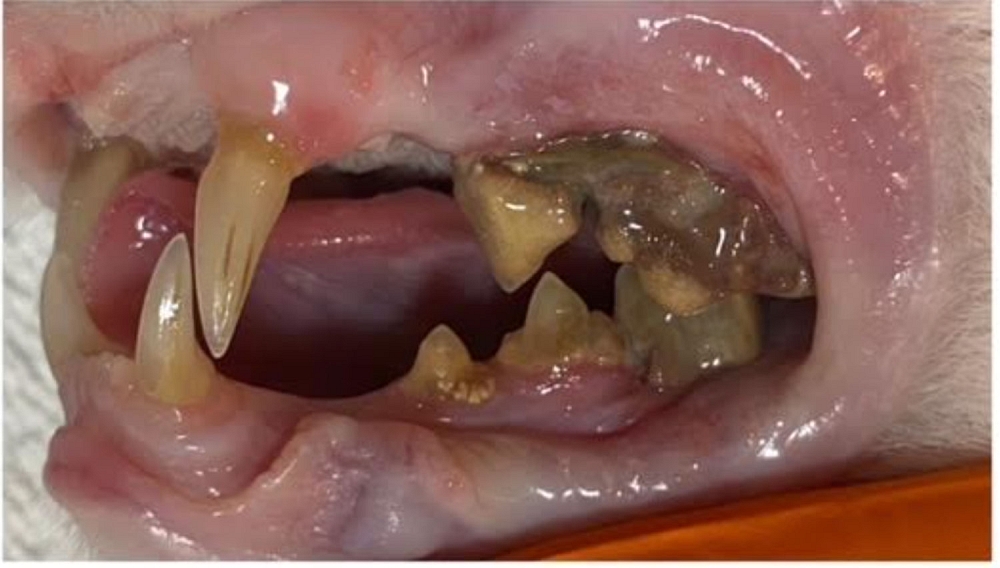

Die grösste Baustelle aber war und ist ihr Gebiss:

Bisher wurde eine Seite behandelt, einige Zähne sind dabei praktisch fast von alleine raus gefallen andere mussten gezogen werden.

Da ihr aufgrund ihres Alters keine zu lange Narkose zugemutet werden sollte, wurde erst eine Seite ihres Gebisses gemacht, die andere Seite folgt in einigen Wochen.

Bereits jetzt speichelt sie weniger und macht allgemein einen besseren Eindruck. Karisma hat vermutlich viele Jahre unter schlimmen Zahnschmerzen gelitten.

Karisma lebte über 16 Jahre auf der Strasse und war nie bei einem Tierarzt. Das hat Spuren hinterlassen. Vor allem an ihrem Gebiss. Jetzt wurde sie umfassend untersucht und ihr Gebiss saniert